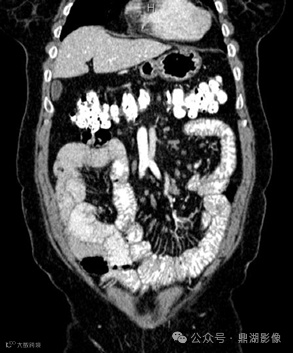

CT增强扫描静脉期

CT小肠造影显示回肠袢轻度扩张,回肠皱襞增多、空肠皱襞减少,并伴有多个肠系膜淋巴结肿大。未发现肠套叠、狭窄或肿块形成等征象。

图2.患者,女,59岁,乳糜泻。静脉注射对比剂增强CT小肠造影冠状位图像显示小肠皱襞模式反转,表现为空肠皱襞数量减少(A中的箭头),这是由于绒毛萎缩所致;回肠皱襞数量增加(B中的箭头),代表回肠空肠化,这是对吸收不良的一种代偿。